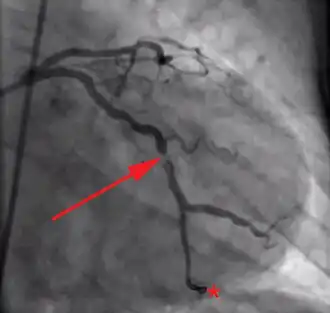

Coronary angiography of a patient with acute myocardial infarction presenting with ST elevation and undergoing primary percutaneous coronary intervention; arrow points at partial occlusion of left circumflex coronary artery; star indicates tip of the guide wire that has been inserted in the artery through the occlusion.

Coronary angiography of the same patient, after dilation of the artery with balloon and placement of stent. The occlusion has been successfully treated.[52]